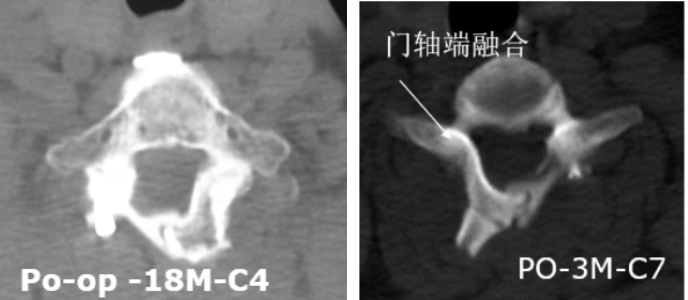

1.最大限度保留并重建后方结构

4.可融合,远期稳定性好